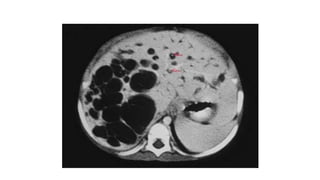

CT Scan

• Useful in identifying type IV & type V disease

CT Scan • Usefulin identifying type IV & type V disease • CT Cholangiography • More sensitive for visualizing biliary tree • More sensitive in detecting choledochal cysts • Less sensitive to characterize pancreatic duct